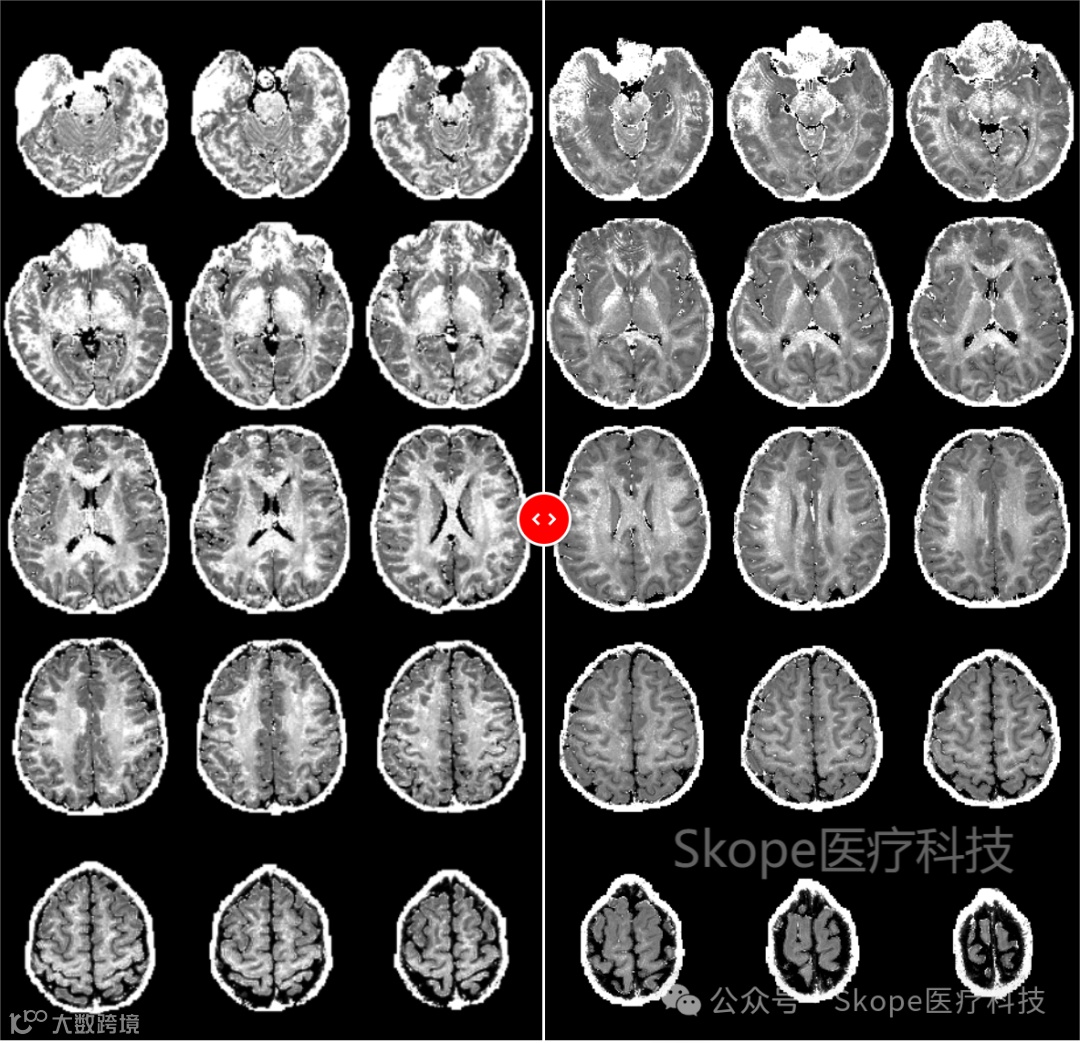

同时,测量实际编码场的能力为选择更具挑战性但高效的读数方案提供了机会。为说明这一点,下图展示了使用两种不同读数技术获取的扩散加权数据导出的细胞内体积分数(ICVF)地图:左侧为回声平面成像(EPI),右侧为螺旋成像。采用螺旋读数的方式可以获得更高的信噪比,直接转化为质量更优越的ICVF地图。

来源:Skope